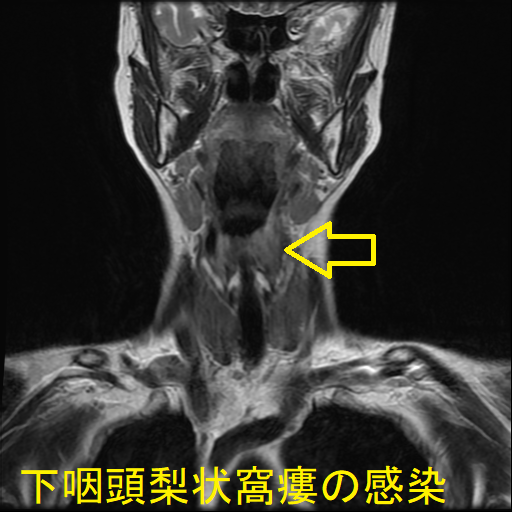

- 通常の造影頸部CTで、甲状腺外の膿瘍形成と、その範囲が明らかになります。

- 下咽頭部造影CTで、下咽頭梨状窩瘻を見つけます。

降下性壊死性縦隔炎とは、歯科治療・扁桃腺炎などによる頚部の深部感染症が、縦隔まで下りてくる病態。発熱・強烈な頚部痛があるものの喉頭ファイバーは異常なし。甲状腺周囲に膿瘍形成することも。亜急性甲状腺炎や急性化膿性甲状腺炎と鑑別[甲状腺超音波エコー検査にて否定]。MRI/CTにて診断可能。胸膜炎や膿胸も来す。敗血症による死亡率高く、早期に縦隔ドレナージ(排膿)。亜急性甲状腺炎と誤診し、ステロイド投与すれば敗血症が増悪。下咽頭梨状窩瘻が甲状腺内でなく、甲状腺周囲に開口している場合、急性化膿性甲状腺炎に至らない。

急性化膿性甲状腺炎に至らない下咽頭梨状窩瘻の感染もあります。下咽頭梨状窩瘻が甲状腺内でなく、甲状腺周囲に開口している場合に起こります。